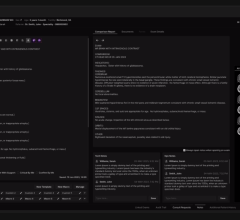

SPONSORED CONTENT — EnsightTM 2.0 is the newest version of Enlitic’s data standardization software framework. Ensight is ...

SPONSORED CONTENT — EnsightTM 2.0 is the newest version of Enlitic’s data standardization software framework. Ensight is ...

Did you know that approximately one-third of all the data in world is created by the healthcare industry and that ...